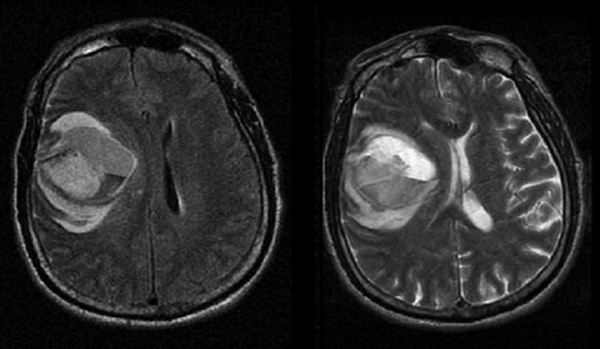

Опухоль головного мозга

МРТ при опухоли головного мозга дает возможность увидеть образование.

Изображение мозга на МРТ после кровоизлияния в опухоль

Своевременное обследование помогает выявить заболевание на ранних стадиях, что предотвращает развитие осложнений и дает шанс на быстрое излечение.